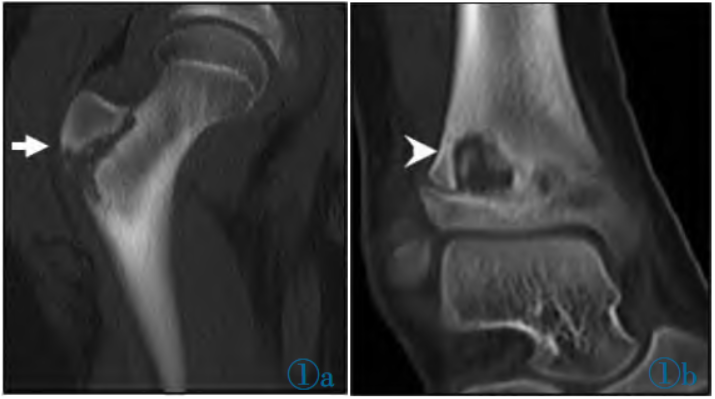

图1CT:右股骨近端(实心箭头A)和右踝处(箭头B)可见不规则骨质破坏,局部骨皮质变薄,内见点状高密度影,邻近骨质可见骨膜反应,周围软组织肿胀。